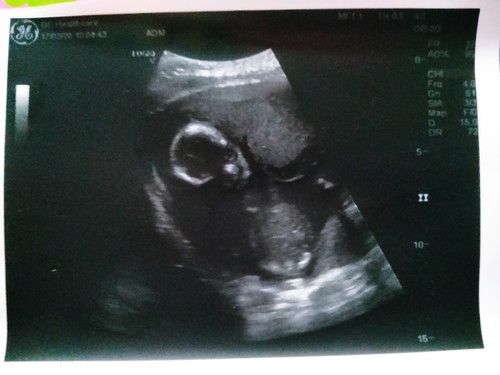

ไปซาวด์แต่หมอให้แค่รูปนี้มา ไม่เห็นมีรายละเอียดอะไรเลยค่ะ 19 week แล้ว

ถ่ายชัดกว่านี้ได้มั้ยคะแม่ ในใบซาวด์จะมีรายละเอียดอยู่นะคะ เช่นลูกกี่วีค นน สส ขนาด เท่าไหร่